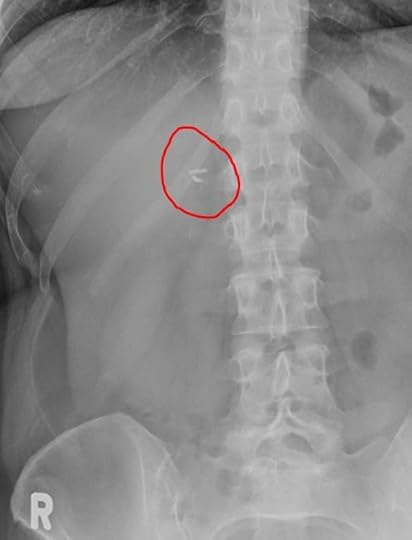

And how did I arrive at this horrifying conclusion? Well, I recently had an abdominal X-ray for another, completely unrelated matter, and on Thursday, I was able to access the report through the radiology clinic dashboard. It was pretty humdrum, and I was getting more than a little miffed once again at the liberal use of the term “unremarkable” (although I was pleased to note that my lungs are apparently “well-aerated”) when it said this: Cholecystectomy clips noted. I was like “What the f*ck is a chole-thingy?” so I googled it, and it’s when you have your gall bladder removed, and I did that about 15 years ago. I realize I’ve just made it sound like I reached into my own abdominal cavity and pulled it out myself, and if that did indeed happen, you will note that I would have accompanied the pulling out of my gall bladder with a flourish and the words Abracadabra, but a surgeon did it, and he was a terrible magician. And I KNOW this because in the same way that a terrible magician would accidentally sit on the top hat and kill his rabbit, this person left METAL CLIPS inside my body. I’ve been setting off the airport security alarms for years and telling them it was MY BELT when, in fact, I am a human IED.

These are my insidesAccording to my research, there are different kinds of clips for this—some dissolve and some are permanent, but the issue is that no one even asked me if I wanted to become a cyborg, and normally I would have said YES, but in this case, there’s no upside—I mean, it’s nothing AT ALL like having forklift arms, and I was initially very upset (not to mention worried that the MRI maybe dislodged them, and now I was being slowly stabbed to death from the inside), but then we went to the see the new Suicide Squad movie. There was a variety of new characters, including a guy called Polka Dot Man, who could shoot polka dots out of his body and eviscerate people with them. Polka dots are a stupid weapon, but you know what’s not? METAL CLIPS. So now I’m going to write to James Gunn and suggest that, for the Suicide Squad sequel, there should be a new character introduced. Her name is Heavy Metal and her superpower is shooting sharp pieces of steel out of her body: